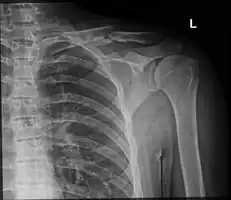

The basic method to check for a clavicle fracture is by an X-ray of the clavicle to determine the fracture type and extent of injury. In former times, X-rays were taken of both clavicle bones for comparison purposes. Due to the curved shape in a tilted plane X-rays are typically oriented with ~15° upwards facing tilt from the front. In more severe cases, a computerized tomography (CT) or magnetic resonance imaging (MRI) scan is taken. However, the standard method of diagnosis through ultrasound imaging performed in the emergency room may be equally accurate in children.[6]

Clavicle fracture